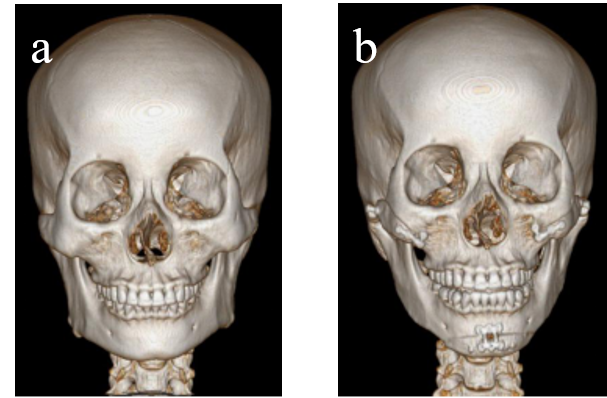

Figure 1. Surgical correction of maxillary retrusion with mandibular protrusion. a: preoperative frontal CT image. b: preoperative digital design and simulation. c: postoperative frontal CT image. d: preoperative lateral CT image. e: preoperative digital design and simulation. f: postoperative lateral CT image.